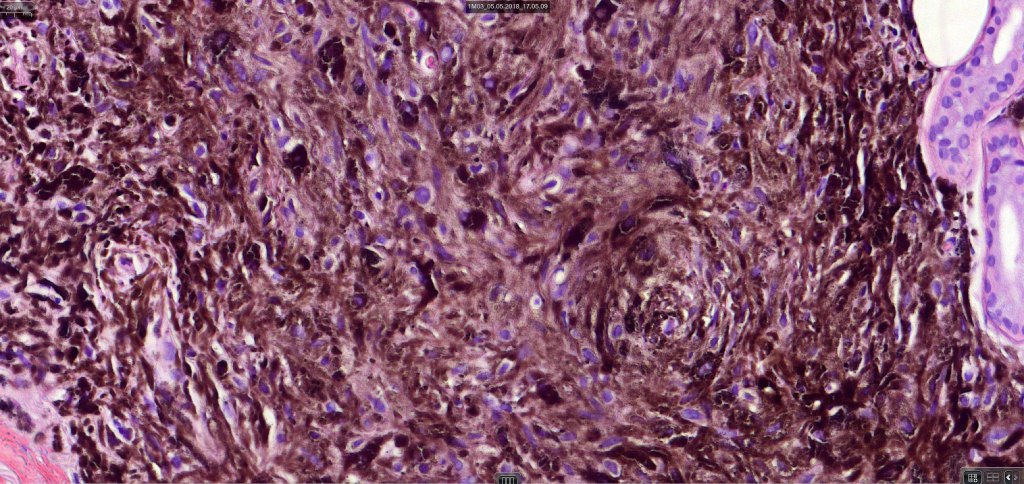

Atpical blue nevus

This is exceedingly rare and the diagnosis should be used very sparingly. It is likely quite benign although very occasionally, a sentinel node biopsy is positive. Great care must be taken to make sure that a blue nevus-like melanoma isn’t missed. It shows the low power features of a blue nevus but high power scrutiny reaveals pleomorphism, nuclear hyperchromatism and increased mitotic activiy (<1 sq mm). Abnormal mitoses are absent as is necrosis. Perineural involvement can be seen but lymphovascular invasion is absent.